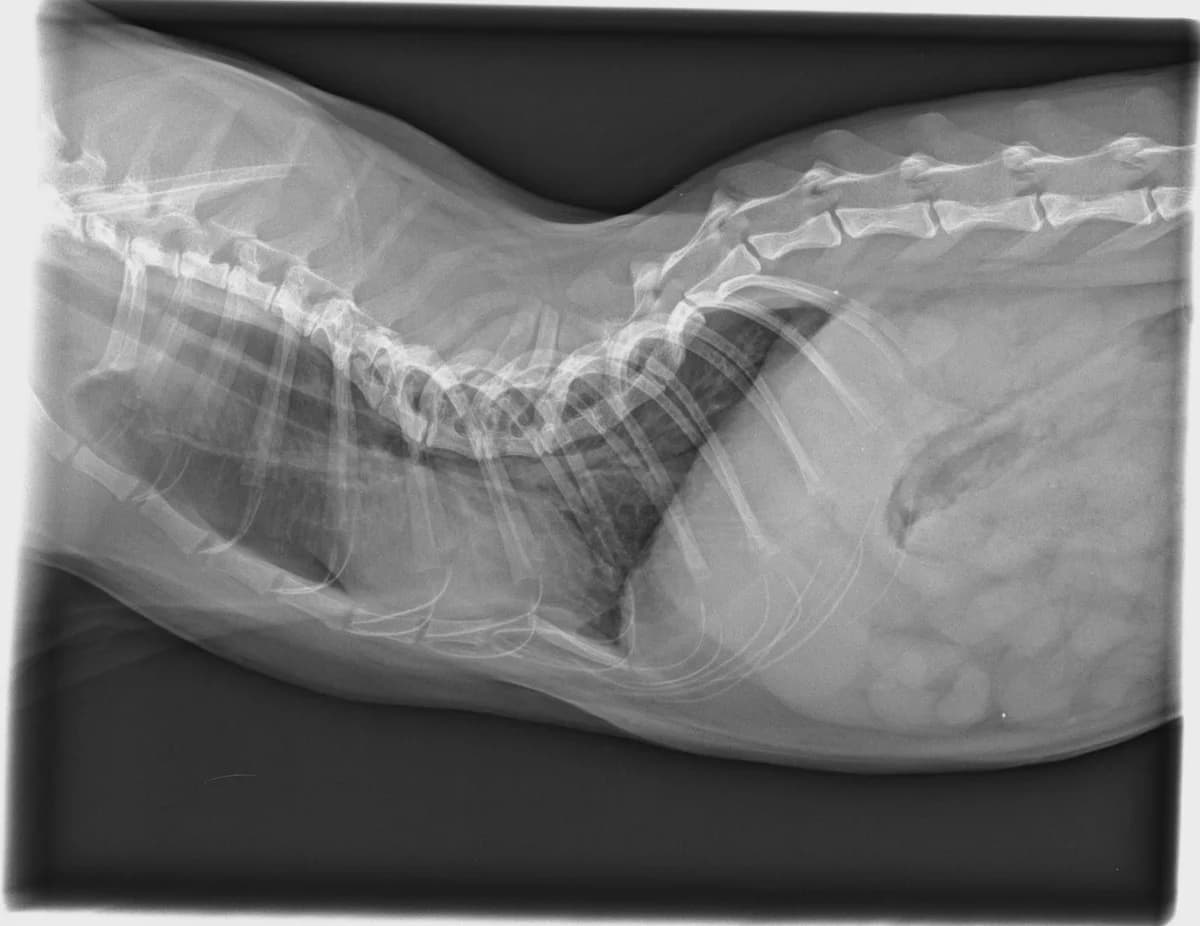

Higuerín sigue esperando su oportunidad. Es un gato tímido pero muy bueno, solo hay que darle su espacio. Fue abandonado en una colonia con una grave lesión de espalda que no tiene operación, pero él se apaña y hace vida normal como cualquier gato. Lleva con nosotros 3 años de los 5 que va a cumplir y ya es hora de tener un hogar y formar parte de una familia. Se lleva bien con otros gatos, aunque a veces sea un poco mandón, aunque no le importaría ser el único y mimado de la casa. Si eres gater@ tienes que venir a conocer a Higuerín. Contáctanos a